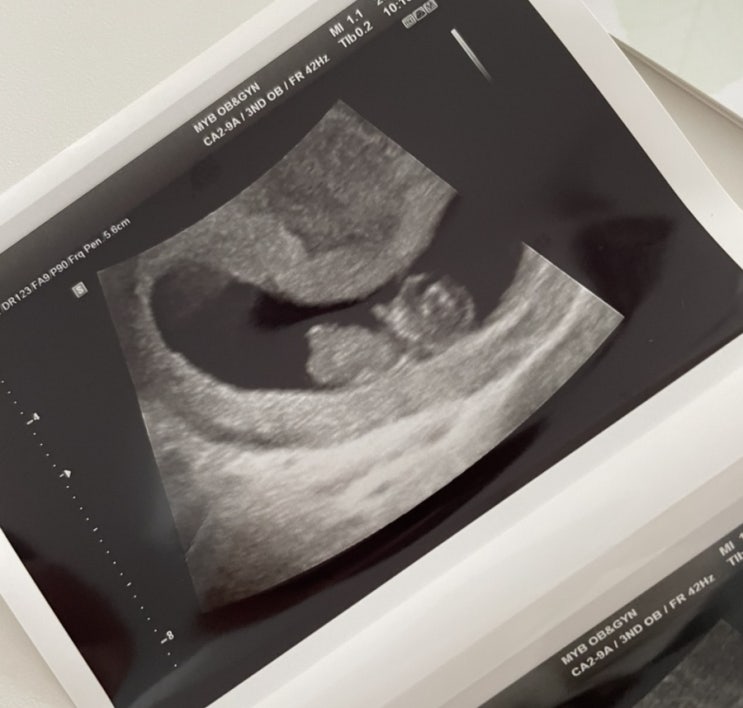

11주 홍삼이, 각도법?!

오늘은 사실 병원가는 날이 아닌데 갑자기 배가 너무 찌르듯 아파서 급하게 병원에 다녀왔다!! 다행히 별일...